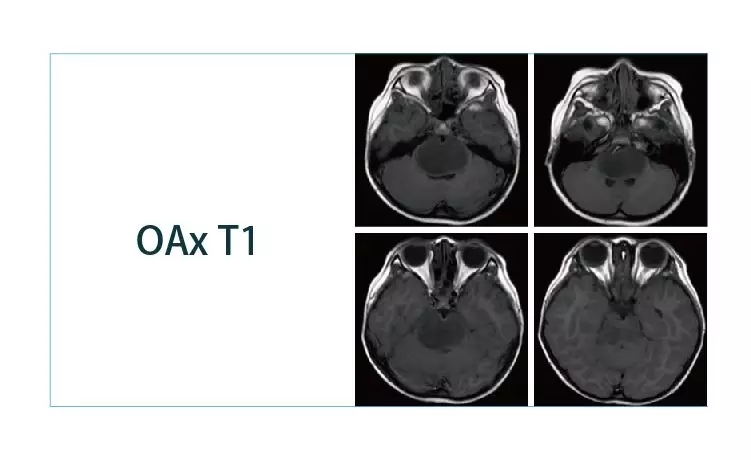

【朗润影像档案】磁共振影像病例分享(编号20190329)

2019-04-01 09:13:05